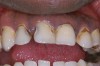

Replacement of existing restorations is responsible for 75% of all operative dentistry.15,19 The reasons for placement and replacement of restorations of direct restorative materials include: primary caries (Figure 1 and Figure 2); recurrent caries (Figure 3); poor margins (Figure 4 and Figure 5); restoration fracture (Figure 6 and Figure 7); tooth fracture (Figure 8); esthetics (Figure 9); non-carious tooth structure lost (attrition, abrasion, abfraction, erosion) (Figure 10); and pain/sensitivity.

Fig. 9 Discolored, unesthetic Class IV composite resin on the maxillary left central incisor.

Figure 9: Discolored, unesthetic Class IV composite resin on the maxillary left central incisor.

Figure 9